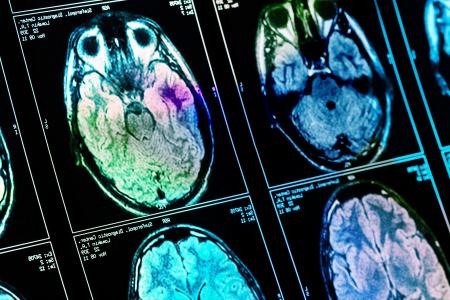

Un seul scanner cérébral suffit

Les médecins utilisent actuellement une série de tests pour diagnostiquer la maladie d'Alzheimer, notamment des tests de mémoire et cognitifs et des scintigraphies cérébrales. Les scans permettent notamment d’évaluer la présence de dépôts de protéines dans le cerveau et le rétrécissement de l'hippocampe, la zone du cerveau liée à la mémoire. Tous ces tests peuvent prendre plusieurs semaines.

La nouvelle approche ne nécessite qu'un seul scanner cérébral d'imagerie par résonance magnétique (IRM) effectué sur une machine standard de 1,5 Tesla, que l'on trouve couramment dans la plupart des hôpitaux. Les chercheurs ont développé un algorithme basé sur

660 caractéristiques différentes pour 115 régions cérébrales.

Parmi ces données figurent la taille, la forme et la texture de chaque région. L’algorithme permet d’identifier les anomalies dans ces caractéristiques, ce qui permet de prédire avec précision l'existence de la maladie d'Alzheimer. Testée sur des scintigraphies cérébrales de plus de 400 patients atteints de la maladie d'Alzheimer à un stade précoce et avancé, de témoins sains et de patients souffrant d'autres affections neurologiques, notamment de démence frontotemporale et de maladie de Parkinson, l’approche démontre sa capacité de détection, et sa précision. Le nouveau système permet de repérer également des changements dans des zones du cerveau qui n'étaient pas jusque-là associées à la maladie d'Alzheimer, notamment le cervelet (la partie du cerveau qui coordonne et régule l'activité physique) et le diencéphale ventral (lié aux sens, à la vue et à l'ouïe)- ce qui ouvre de nouvelles voies de recherche sur l’étiologie la maladie d'Alzheimer.